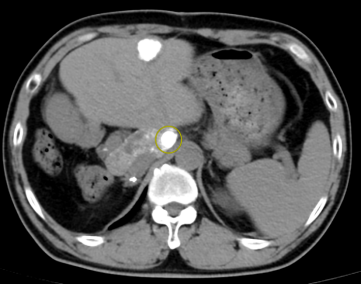

发现本次复发肿瘤病灶位于肝尾状叶

其位置位于腹腔深部

且后方为腹主动脉这一人体重要血管

肝尾状叶肿瘤病灶